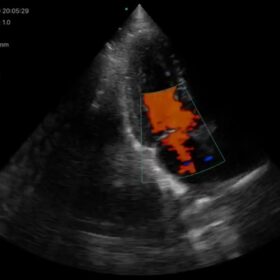

Cardio 2D, Color and PW doppler